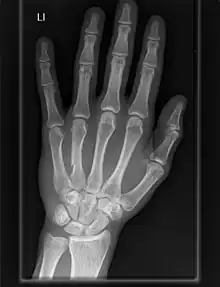

Carpometacarpal joint

The carpometacarpal (CMC) joints are five joints in the wrist that articulate the distal row of carpal bones and the proximal bases of the five metacarpal bones.

The CMC joint of the thumb or the first CMC joint, also known as the trapeziometacarpal (TMC) joint, differs significantly from the other four CMC joints and is therefore described separately.

Fingers

- The second metacarpal articulates primarily with the trapezoid and secondarily with the trapezium and capitate.

- The third metacarpal articulates primarily with the capitate,

- The fourth metacarpal articulates with the capitate and hamate.

- The fifth metacarpal articulates with the hamate.